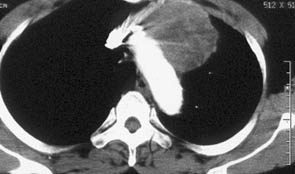

纵隔胸腺肿瘤。CT增强纵隔窗示右前纵隔软组织密度肿块(标记),有强化表现。中心密度略低。

CT平扫:中纵隔气管分杈前间隙内见一巨大软组织肿块,最大径约10.5×8.0cm,密度不均。其后方左主支气管轻度受压,左外侧穿过主动脉窗伸入主动脉弓左旁隙。上缘达胸锁关节水平,下缘达第七胸椎水平。心包前缘见少量积液征